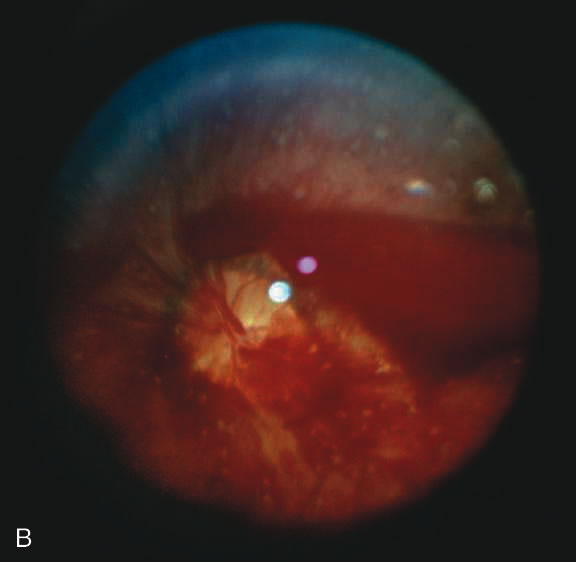

Findings range from a normal fundus to a small number of scattered intraretinal hemorrhages in the posterior pole to massive, confluent hemorrhages from the posterior pole to the ora serrata.(Fig. 10) The hemorrhages may be subretinal, deep intraretinal (dot/blot), nerve fiber layer (flame shaped) or preretinal.19,45 Intraretinal hemorrhages are more common than preretinal or subretinal hemorrhages.32,46 Preretinal hemorrhages must be distinguished from traumatic retinoschisis (see later), which has particular diagnostic significance. White-centered retinal hemorrhages, although classically associated with endocarditis, can occur in any condition that causes retinal hemorrhages, including SBS. Vitreous hemorrhage may be small to massive, and may occur secondary to escape of blood from intraretinal collections or from torn vessels.19 Although vitreous hemorrhage may occur at the time of injury, it may also be a delayed finding occurring 1 to 3 days or more after the initial trauma.47,48

The pathophysiologic mechanisms of retinal hemorrhage in SBS are varied. Vitreous and perhaps orbital shaking is likely to be involved in most of the vitreoretinal injuries. In children, the vitreous is well attached to the retina at the macula, blood vessels, and the periphery. Shaking of an infant causes the vitreous to shake, which, in turn, applies shearing forces to the retina at points of firm attachment. These shearing forces at the macula may split the retina at any layer, causing the formation of a cystic cavity, which may be filled partially or completely with blood (Fig. 11). This traumatic retinoschisis has been well documented in abuse cases by ultrasound, electroretinogram, and pathology.34,58,60,61,62,63,64 Histopathology reveals a widening of the retinal layers or a stripping of the internal limiting membrane. The vitreous may stay adherent or detach. Clinically, to recognize this important finding in SBS, the examiner may observe a hemorrhagic or hypopigmented curvilinear edge to the schisis cavity, with or without a fold in the retina (Figure 11).50,65,66 Recognition of this edge helps distinguish retinoschisis from subhyaloid hemorrhage. However, subhyaloid hemorrhage, which may have originated from blood breaking out of a schisis cavity, may obscure the underlying schisis. It is important to follow any potentially shaken child with preretinal blood in the macula until that blood has cleared as the signs of schisis may be unmasked as the blood resorbs thus confirming the diagnosis of SBS. The retinal fold or hypopigmented line may be a complete circle or just an arc. In the long term, these patients may have surprisingly few sequelae and good vision as the cavity flattens spontaneously. There may also be findings of permanent curvilinear, hypopigmented scars or retinal folds. These provide clues to prior abuse.67

There remain still other theories for retinal hemorrhage in SBS that also seem to play a minor role. Some have suggested a Purtscher-like mechanism due to an increase in intrathoracic pressure when the perpetrator squeezes the child's chest. Although the characteristic white retinal patches of Purtscher retinopathy may be seen in SBS (Fig. 11), there appears to be no correlation with rib fractures,35 and the finding is very uncommon. The failure to see significant retinal hemorrhaging after the chest compressions of cardiopulmonary resuscitation in both animal models and humans also argues against a Purtscher-like mechanism.

Caretakers often relate histories of relatively minor head trauma as the cause of injuries that are otherwise generating the suspicion of SBS.21,34 After much study, most authors88–90 conclude that severe injury after a minor fall should raise the suspicion that the history is false and that the child has been abused. Furthermore, “most investigators agree that trivial forces such as those involving routine play, infant swings, or falls from a low height are insufficient to cause” the injuries seen in SBS.21,91 Even severe accidental head injury such as depressed skull fracture or intracranial hemorrhage does not routinely cause retinal hemorrhages.90,92,93 In compiling the available literature, retinal hemorrhage occurs in less than 3% of accidental head trauma, and then, almost always only in cases of severe, life-threatening injury.35,53,72,91,92,94,95 In the few cases of accidental head trauma with retinal hemorrhage, the bleeding is confined to the posterior pole with dot-blot, flame-shaped, or preretinal hemorrhages. Occasionally, these hemorrhages can extend to the midperiphery. But even the most severe accidental head trauma injuries do not cause the extensive retinal hemorrhages seen in SBS, except perhaps when the injury mechanism involves multiple acceleration-deceleration events such a motor vehicle accident in which the car strikes several objects or rolls consecutively resulting in death of the child. Retinochisis has not been observed after accidental head trauma, although there is one case of a child who may have suffered a severe crush injury to the head (five skull fractures with brain extrusion) and also a few adults with other causes of injury who have been observed to have paramacular folds or subinternal limiting membrane hemorrhage. These cases should not be taken to imply that in the SBS age range, macular schisis has a differential diagnosis other than SBS.